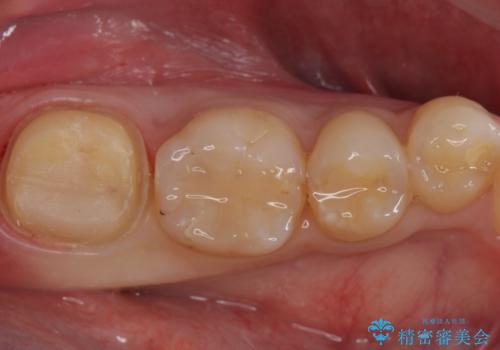

- 左下7 生活歯髄療法:33,000円 仮歯+ジルコニアクラウン:11,000円+121,000円費用は治療当時の料金となります

虫歯が大きくても、今回のように神経を温存することができる場合があります。